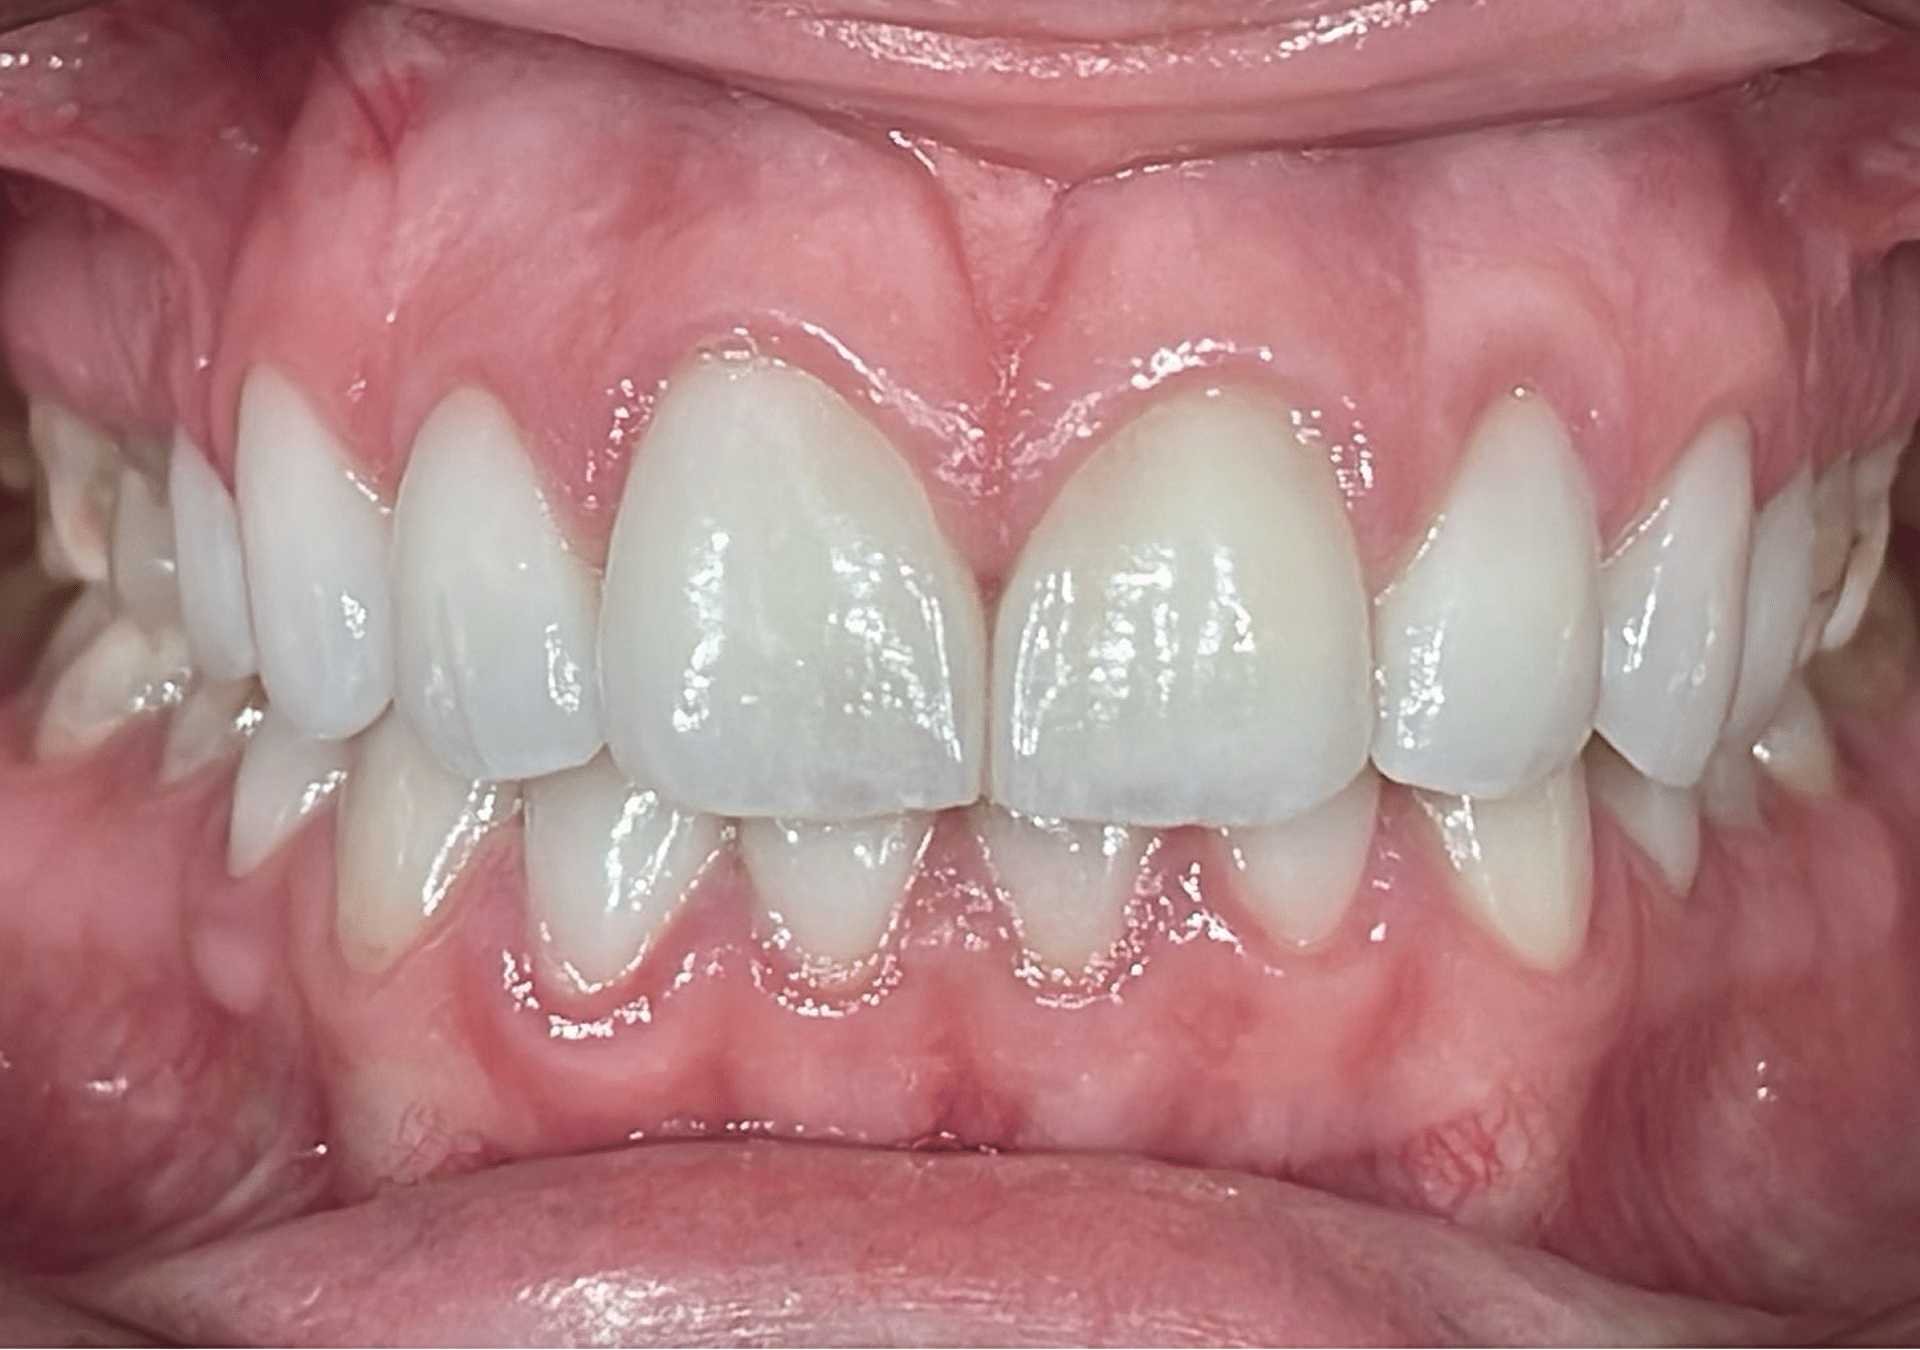

Caso 2

Rehabilitación con cerámica feldespática de paciente con amelogénesis imperfecta (esmalte defectuoso), eliminación de tinciones y protección superficies.